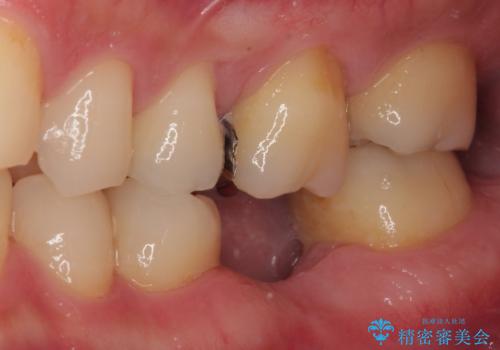

奥歯に歯を入れたい 即時荷重インプラントによる短期間インプラント治療

放置した欠損部 奥歯の即時荷重インプラント治療